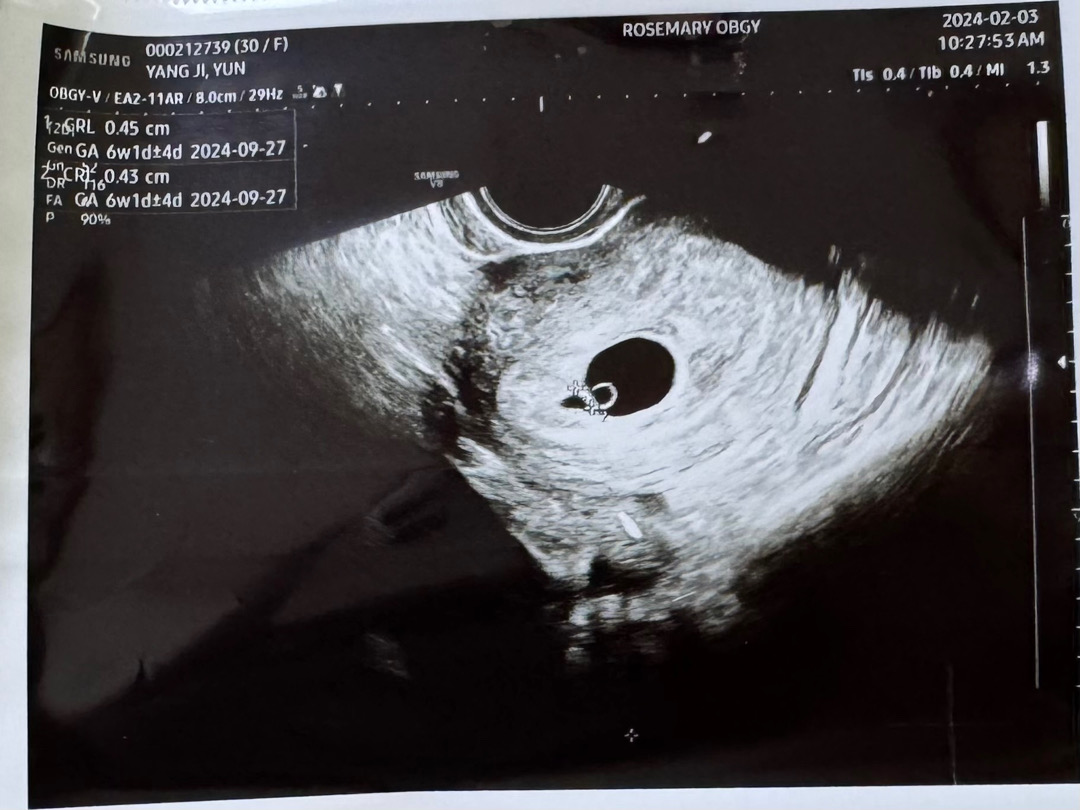

6주 1일 아기심장 소리 듣고왔어요 ♥️

0.45cm라 하시고 심장소리 들으니 마음이 뭉클 하더라구요 >< 다이아몬드가 이렇게 예쁘다니 .. ♥️

네넵 !! ㅋㅋㅋ 들리더라구요 112bpm이였는데 그 0.45cm인데 심장이 반짝반짝 거리더라구요 👍🏻👍🏻 내일 심소 들으셨으면 좋겠어요 ><